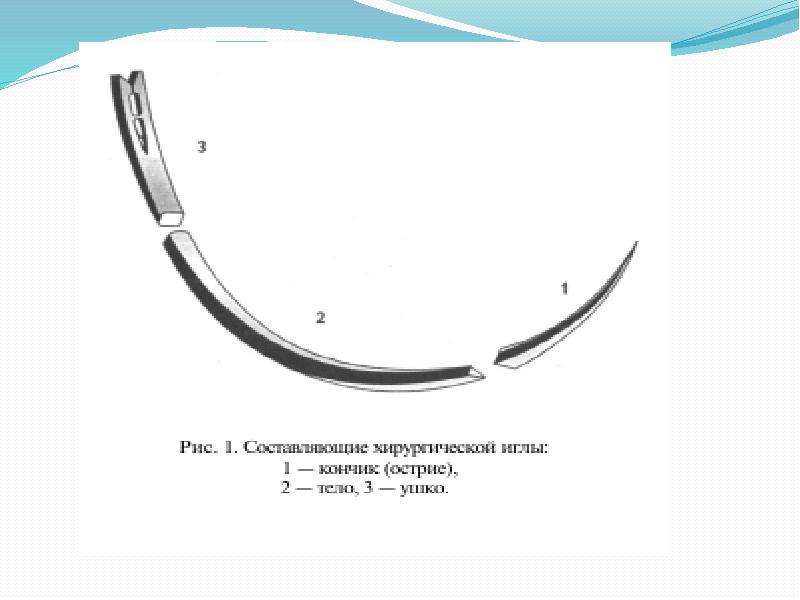

- 3. Иглы